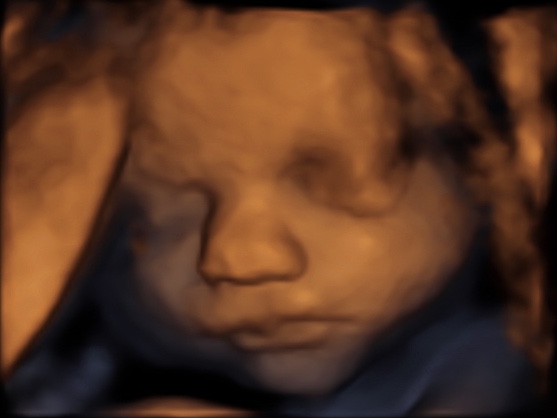

39 weken

Een echo na 39 weken.